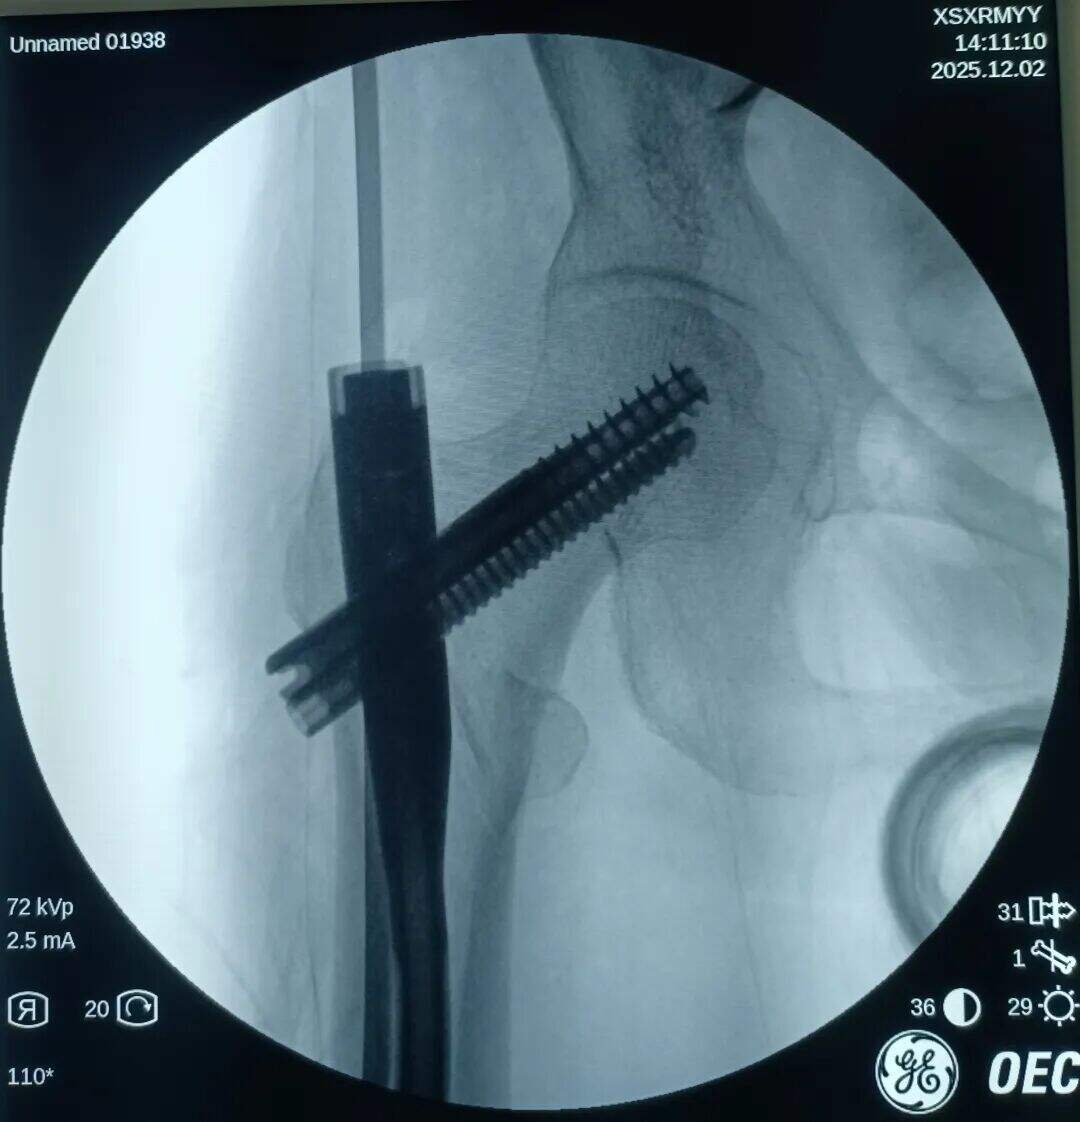

Narezen je bil 2 cm prednji mini-rez. Mesto zloma je bilo opazovano z prstom. Ugotovljeno je bilo, da je proksimalni fragment premaknjen navzgor, distalni fragment pa nazaj in zaklenjen. V mesto zloma je bil vstavljen klešča; pod vodstvom prsta v kombinaciji s kleščo so bili zaklenjeni fragmenti odklenjeni. Nato je bila klešča uporabljena za ohranitev kakovosti redukcije z medialno in lateralno kompresijo. Izvedena je bila običajna lokalizacija, vstavitev vodilne žice ter standardni kirurški postopek.

Medularni kanal je bil ozek. Nobenega razširjanja ni bilo izvedeno. Intramedularni klin s premerom 9 mm je bil vstavljen v tesen fit. Prilagoditev anteversije cefalomedularnega vijaka se je izkazala za težko.